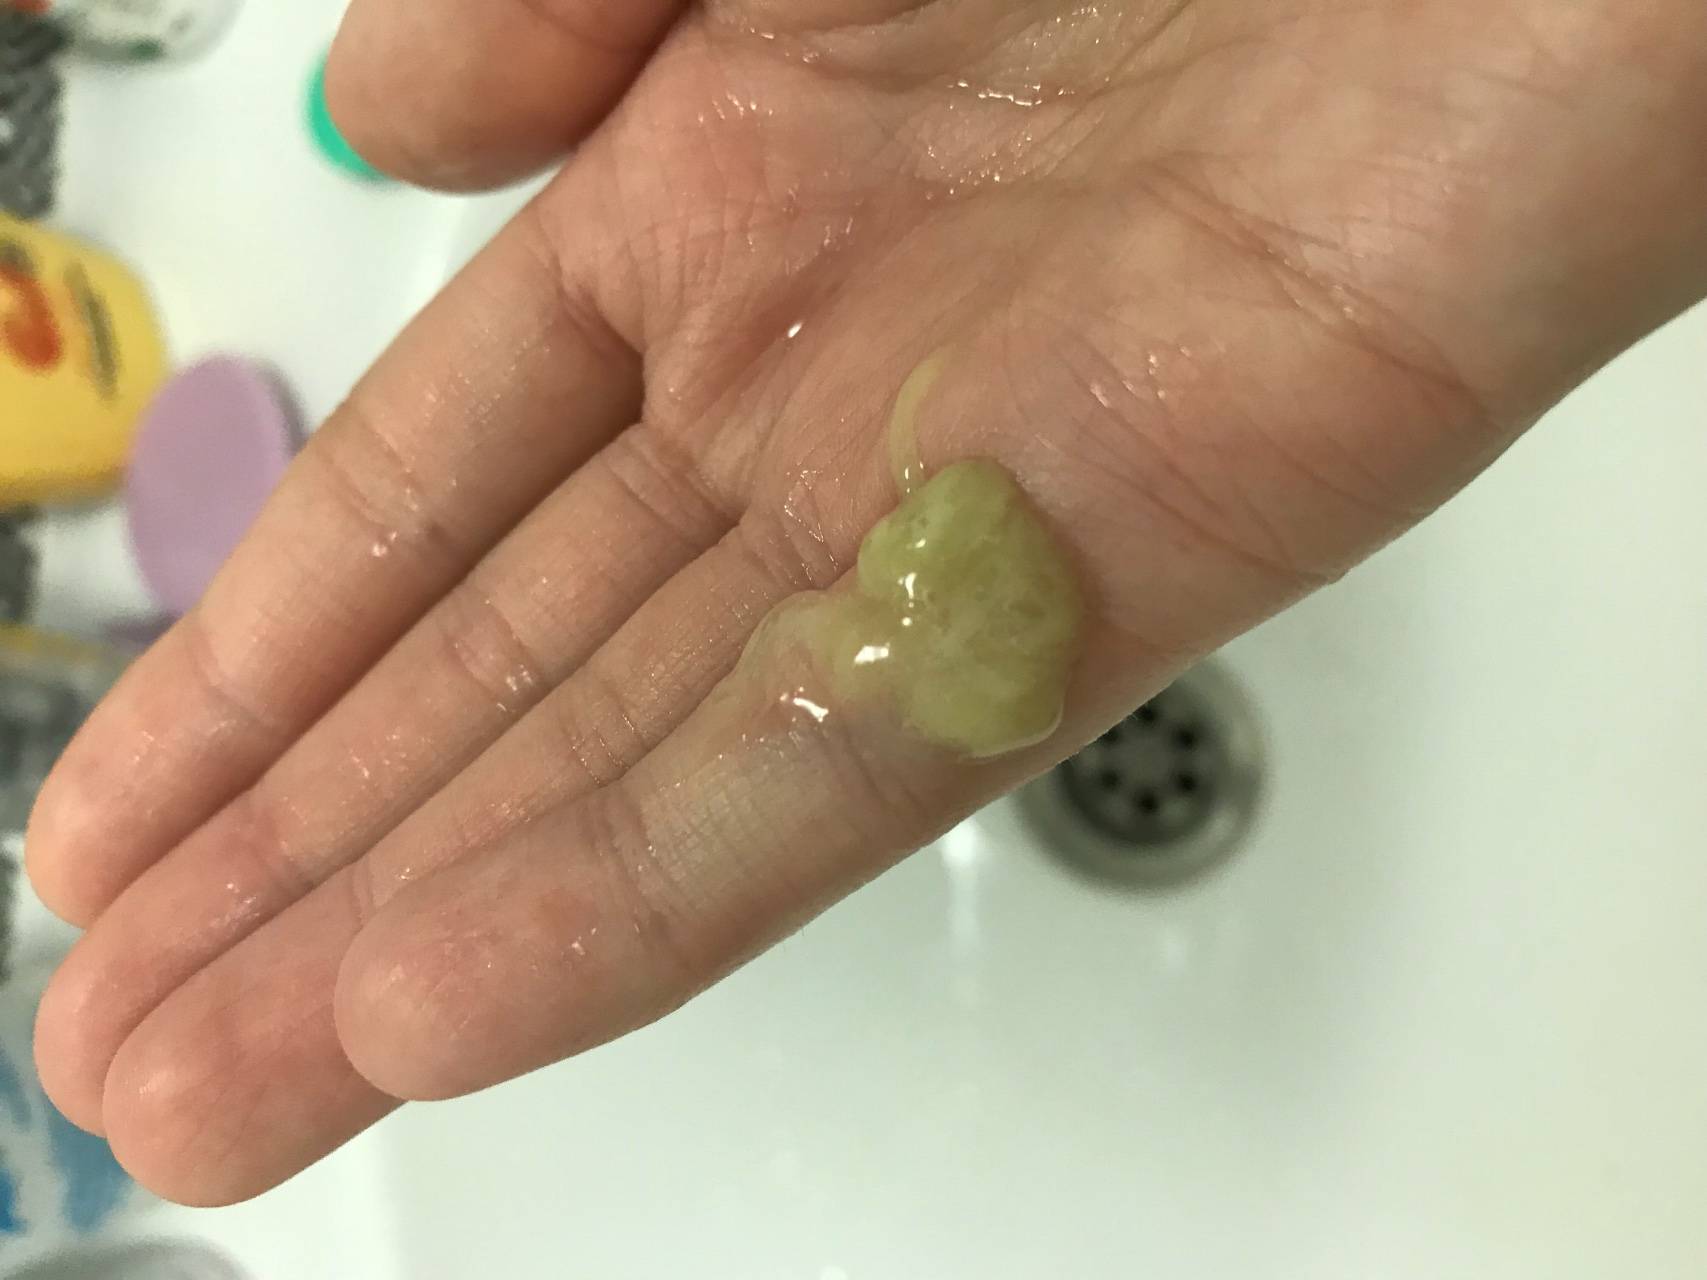

Симптомы и причины скопления воды в легких

Раздел: Ракурсы просвещения